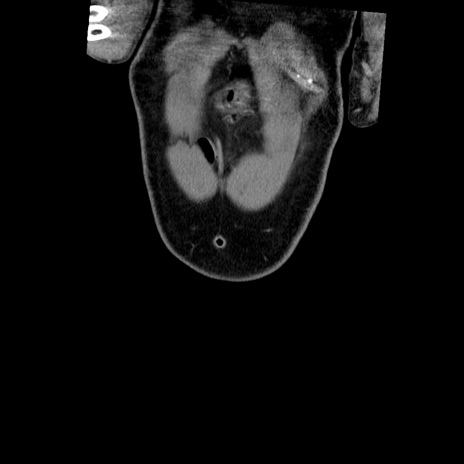

横断像

【症例】50歳代男性

【主訴】腹痛

【現病歴】AVMからの被殻出血のため回復期リハ病棟入院中。 本日午後3時頃急に下腹部痛が出現した。

【身体所見】意識晴明、左半身不全麻痺、会話の理解は良好、36.5°C、腹部:膨隆、全体に板状硬、下腹部正中に圧痛点あり、反跳痛-、筋性防御不明、右下腹部にope scar